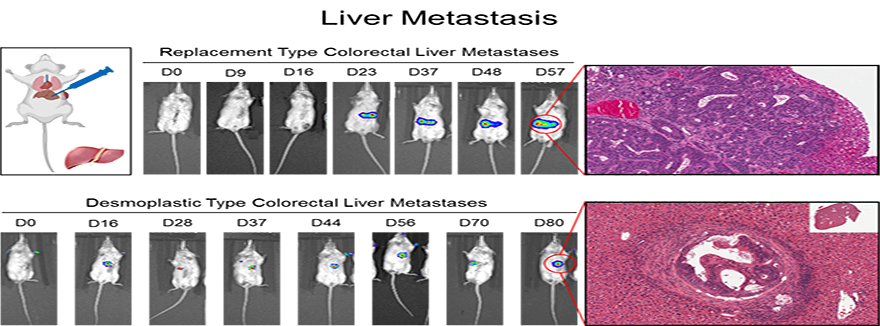

Cancer cells must continually alter their cellular metabolism to cope with changing microenvironments in both the primary tumor and distant metastases. Our work has shown that specific metabolic strategies (glycolytic metabolism, oxidative phosphorylation) enable cancer cells to grow some sites (lung, bone), versus others (liver). We have also shown that cancer cells that exhibit the ability to shift between different metabolic strategies are the cells that are the most metastatic and therapy resistant. Currently, we are examining how distinct metastatic or primary tumor microenvironments influence metabolic wiring in cancer cells.